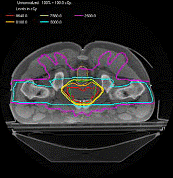

3D适形调强放射治疗设备(3D Conformal and Intensity Modulation-IMRT)

与3D适形放射治疗设备的区别是:3D Conformal仅仅是几何形状的符合,辐射野内的剂量强度是均匀的。而IMRT 则要求不仅几何形状符合,辐射野内的剂量强度也要根据临床要求实时调变。从一定意义上讲,IMRT几乎完美地满足了避免照射和提高肿瘤局部控制率的新要求。